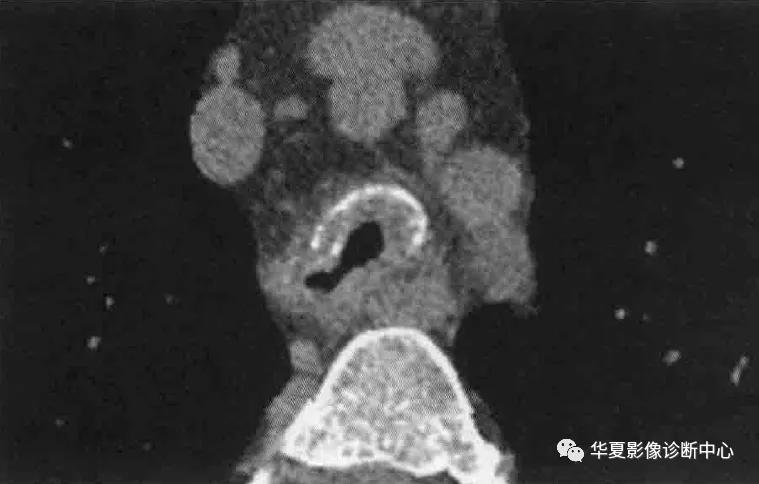

影像学表现:X线大多数患者表现为正常,局限或弥漫性气道增厚伴狭窄很难在X线检查发现;结节样原发肺实质淀粉样变表现为孤立的、直径0.5-1.5mm多发结节,常见于下肺周边部位,进展缓慢;弥漫性肺间质淀粉样变导致王哥庄、结节状或网格结节样改变,主要累及下肺。CT表现包括气道壁局限或弥漫性增厚,管腔狭窄,部分病例可见钙化,支气管受累常并发远端肺不张,支气管扩张或空气潴留;结节样原发肺实质淀粉样变表现为孤立或多发结节,有时可导致巨大团块,CT可见到20-50%的结节有钙化;弥漫性肺间质淀粉样变表现为网格状病变和小叶间隔增厚,多发胸膜下微结节常与网格并存,少部分病例可见磨玻璃或实变,牵拉性支气管扩张等。纵隔和肺门淋巴结肿大多见于L型淀粉全身淀粉样变患者。